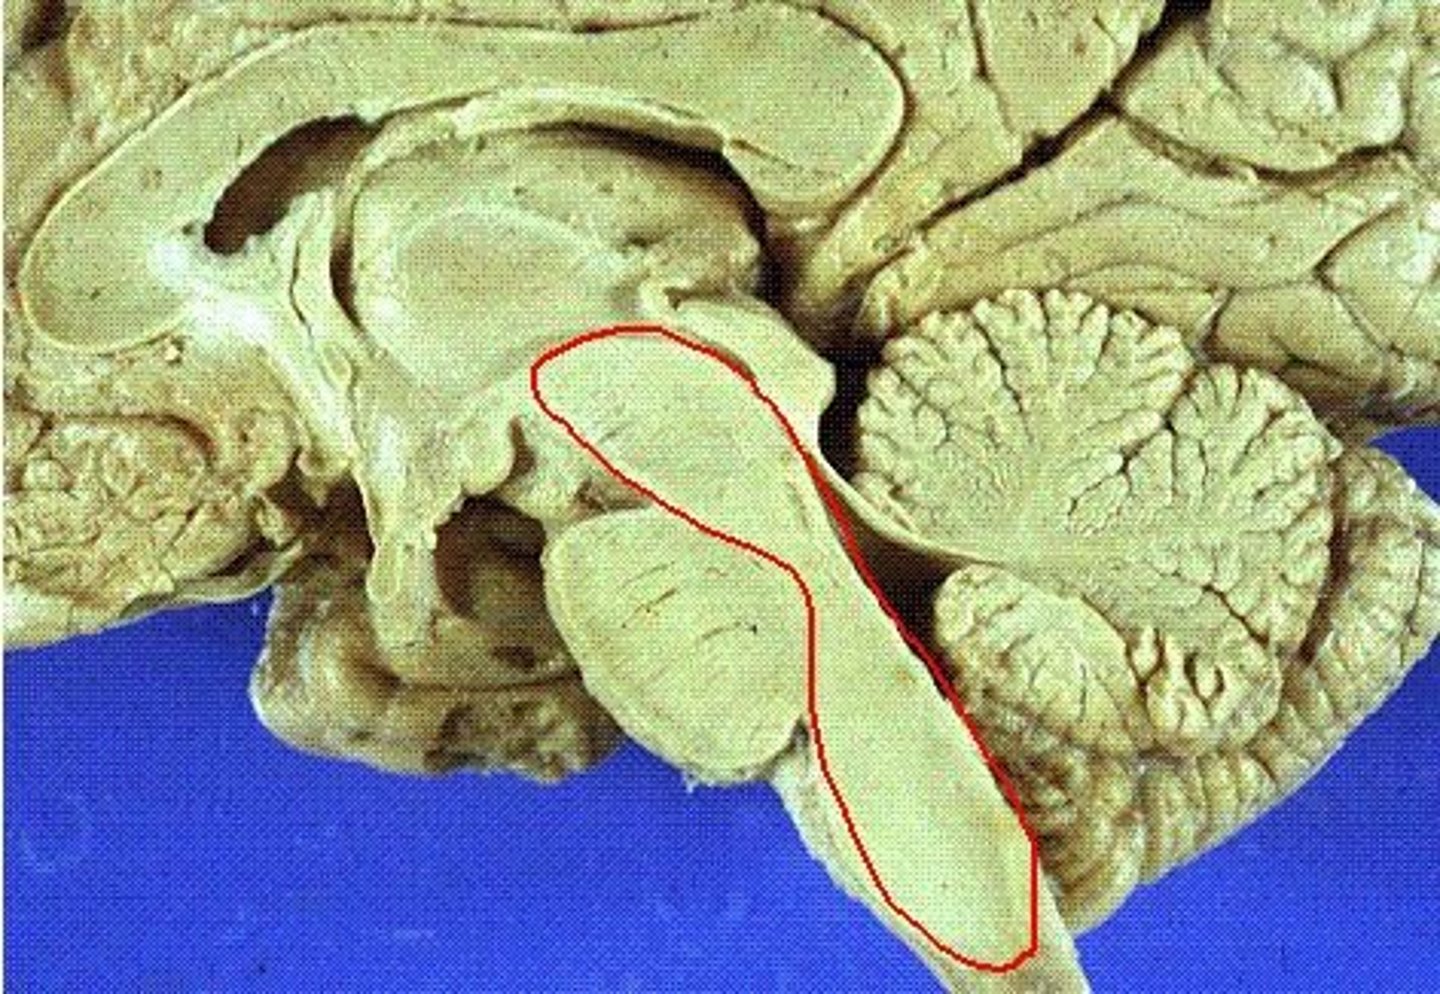

What forms the superior portion of the roof of the 4th ventricle? (A)

superior cerebellar peduncles

inverted V shaped interval between the superior cerebellar peduncles that is filled by a thin layer of white matter

superior medullary velum

lower portion of the roof of the 4th ventricle formed by a thin layer of pia mater and ependymal cells

inferior medullary velum

structure attached to the ventral surface of the inferior medullary velum in the 4th ventricle that helps form CSF

choroid plexus

opening in the caudal aspect of the inferior medullary velum that allows CSF from the 4th ventricle to flow into the cisterna magna of the subarachnoid space

foramen of Magendie (or median aperture)

What mostly forms the lateral walls of the 4th ventricle?

inferior cerebellar peduncles and choroid plexus

openings in the 4th ventricle that allows CSF to flow from the 4th ventricle into the pontine cistern of the subarachnoid space

foramen of von Luschka (or lateral apertures)

A

superior cerebellar peduncles

superior medullary velum

inferior medullary velum